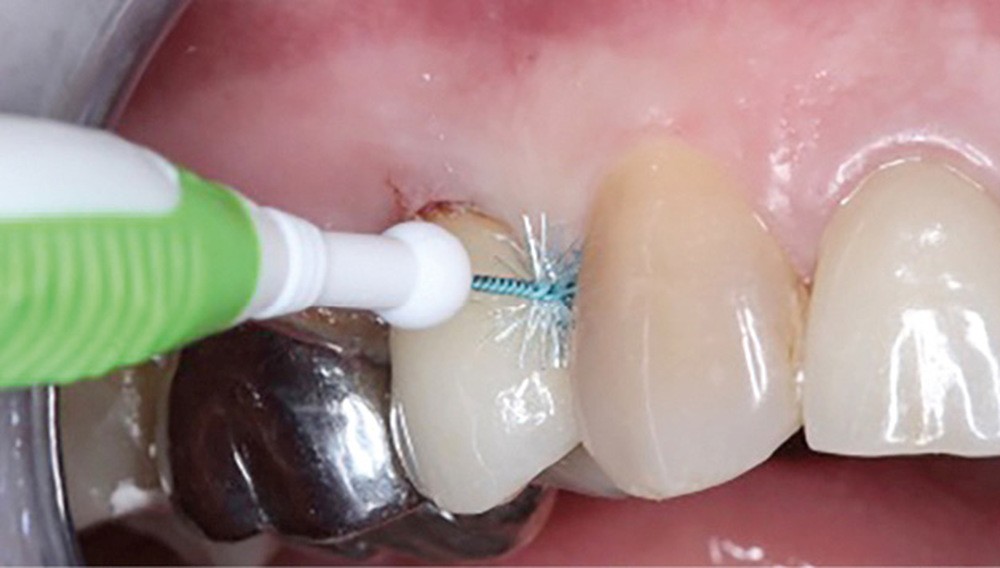

Enfin, la conception prothétique elle-même est à réfléchir, que ce soit en termes de profil d’émergence [18, 19] (pas de surcontour par exemple) (fig. 8) que d’accès à l’hygiène [20, 21] (fig. 9).